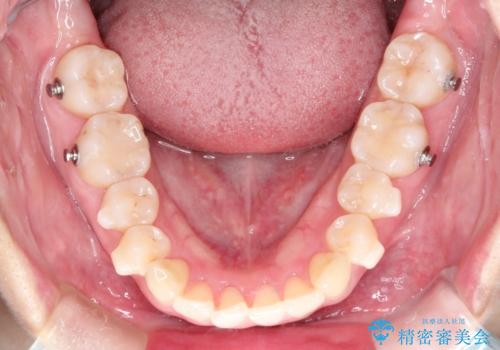

- 前歯の捻れと口元の突出を主訴に来院されました。

インビザラインを用いて上顎の遠心移動を行い、前歯を下げながら凸凹を綺麗に治すことができました。

歯を抜かない矯正治療を行う場合、口元は極端には変わりません。

今回は奥歯の遠心移動を行い、できる限り前歯を下げられるように治療を行いました。